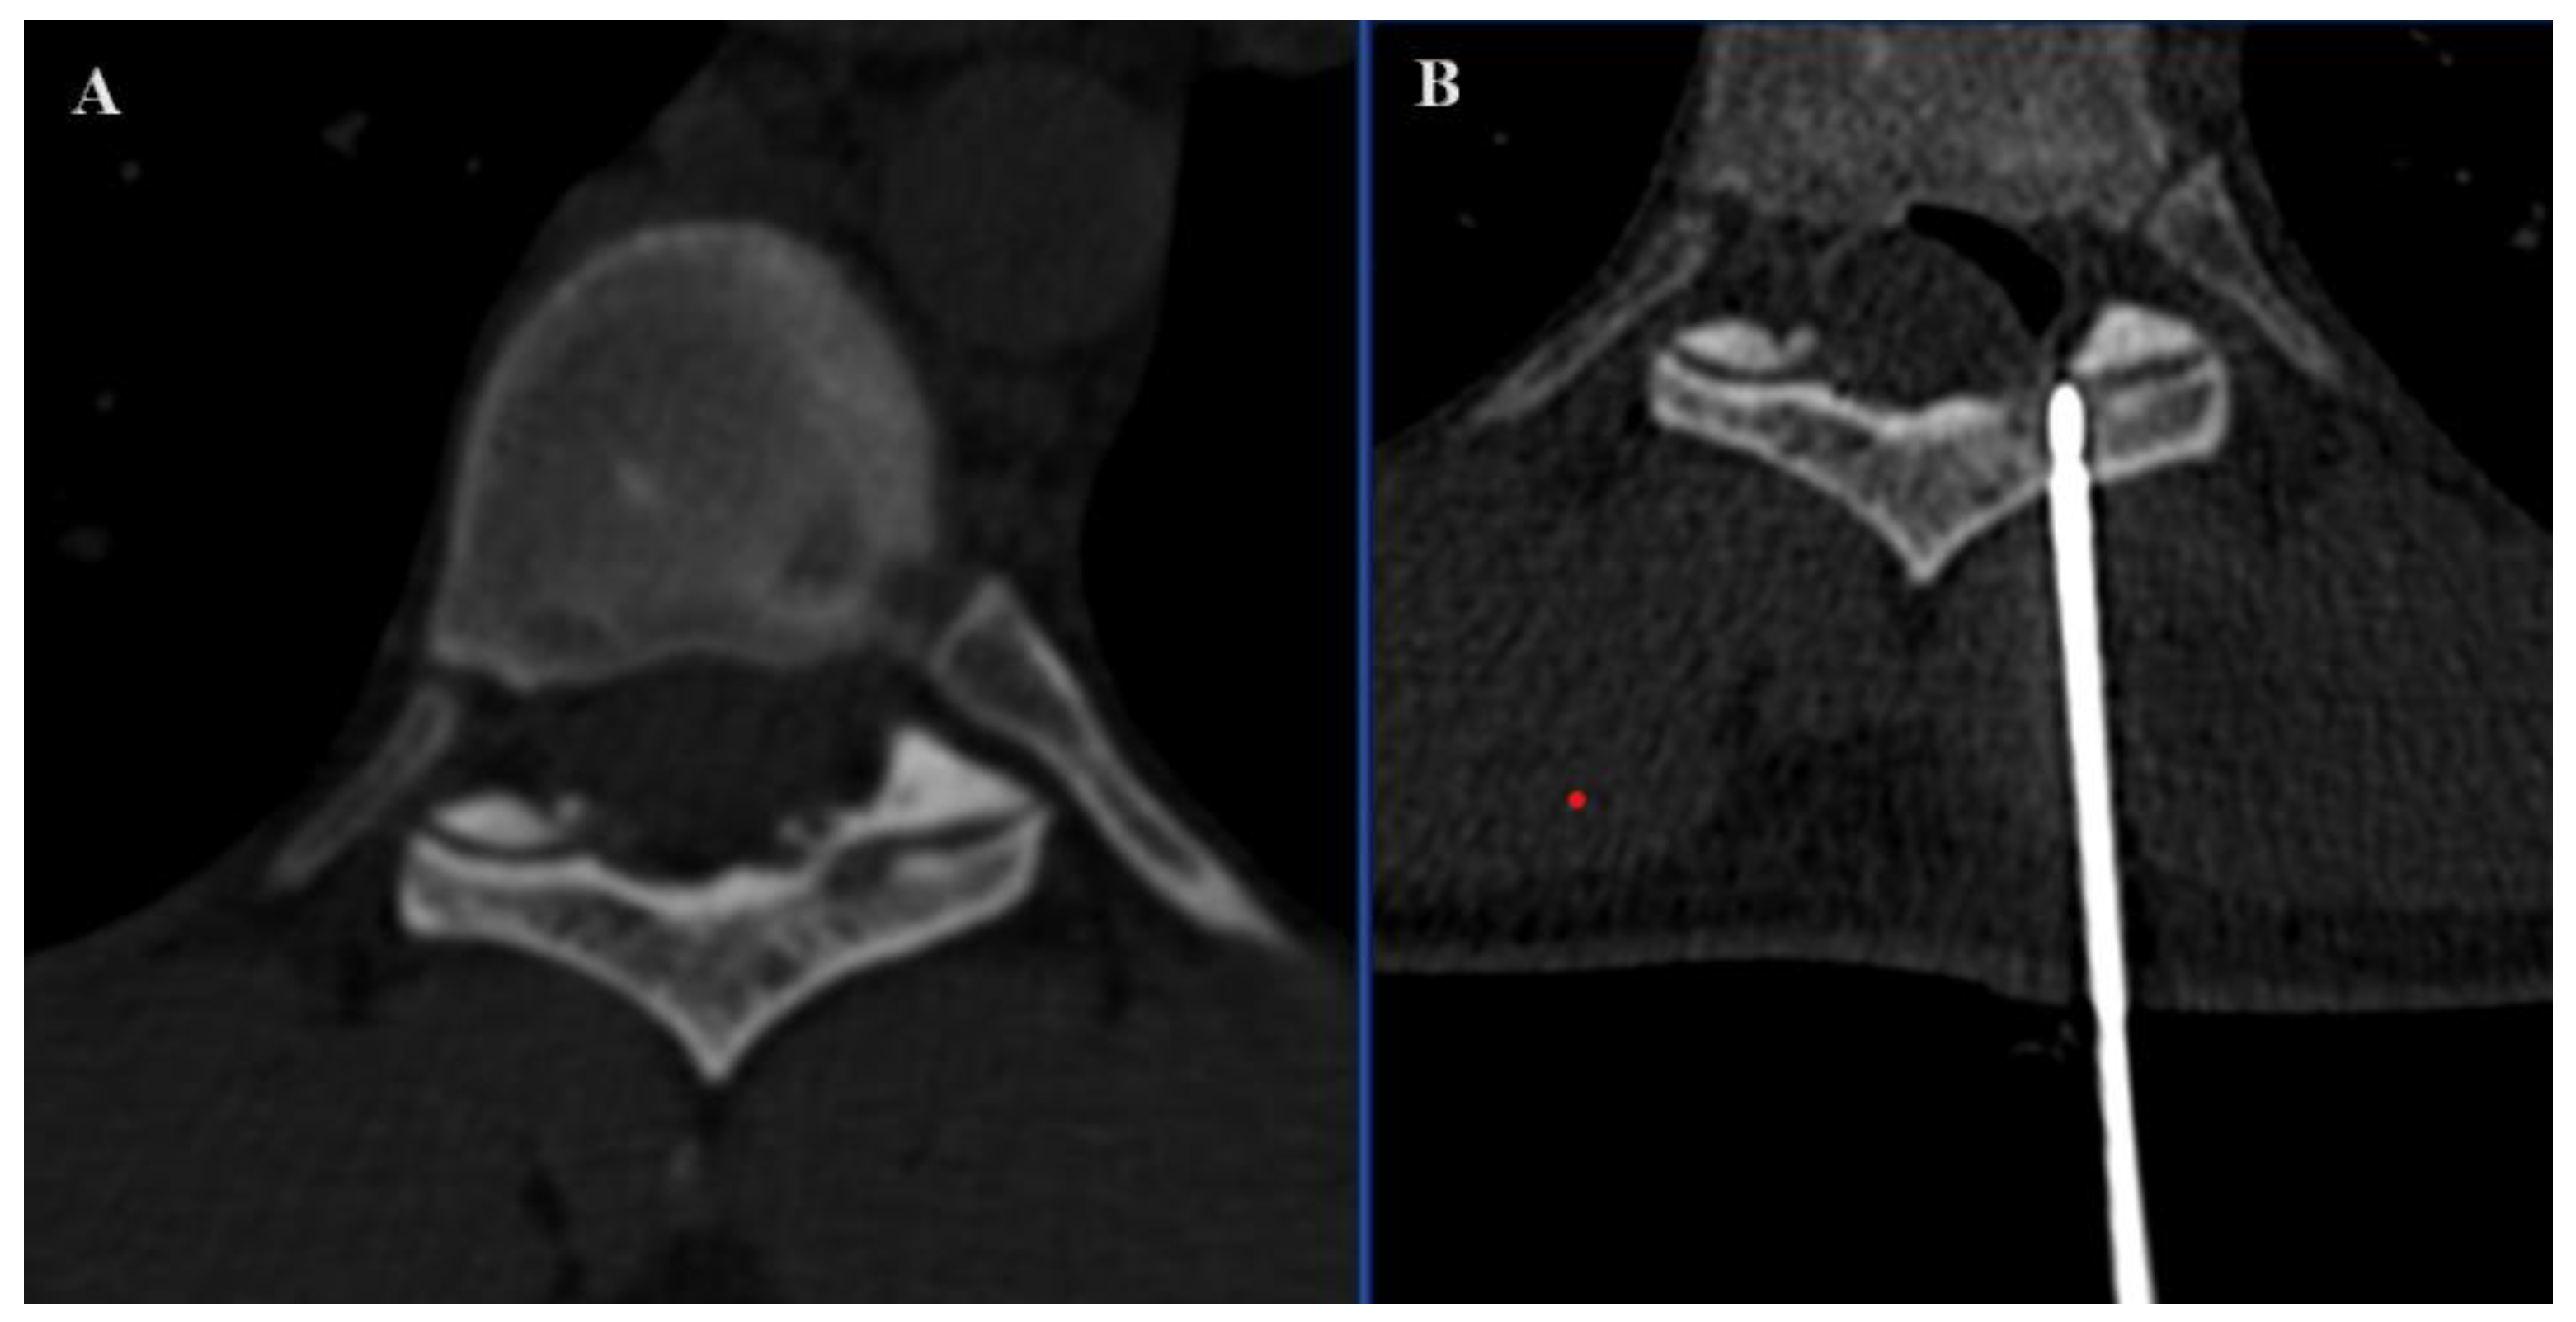

In the SIRIO-assisted group, the SIRIO augmented reality navigation system was used to guide the needle into the lesion with real-time 3D visualization. Standard CT guidance was employed in the non-SIRIO group. Epidural dissection was performed in all procedures through a 22 G needle, using non-ionic 5% dextrose mixed with diluted organ iodine contrast medium and carbon dioxide (Figure 1 and Figure 2), to obtain a multilevel dissection adjacent to the site to be treated. The procedures were performed under similar conditions, with a focus on minimizing radiation exposure and ensuring precision in needle placement. For each patient, medical records, previous imaging exams, laboratory studies, and lesion-related pathological information were carefully evaluated.

Figure 1. Axial (A) image demonstrating a secondary osteolytic lesion from breast cancer located in the spinal process of D8. Sagittal (B) and axial (C) images showing epidural dissection with CO2 and contrast medium.